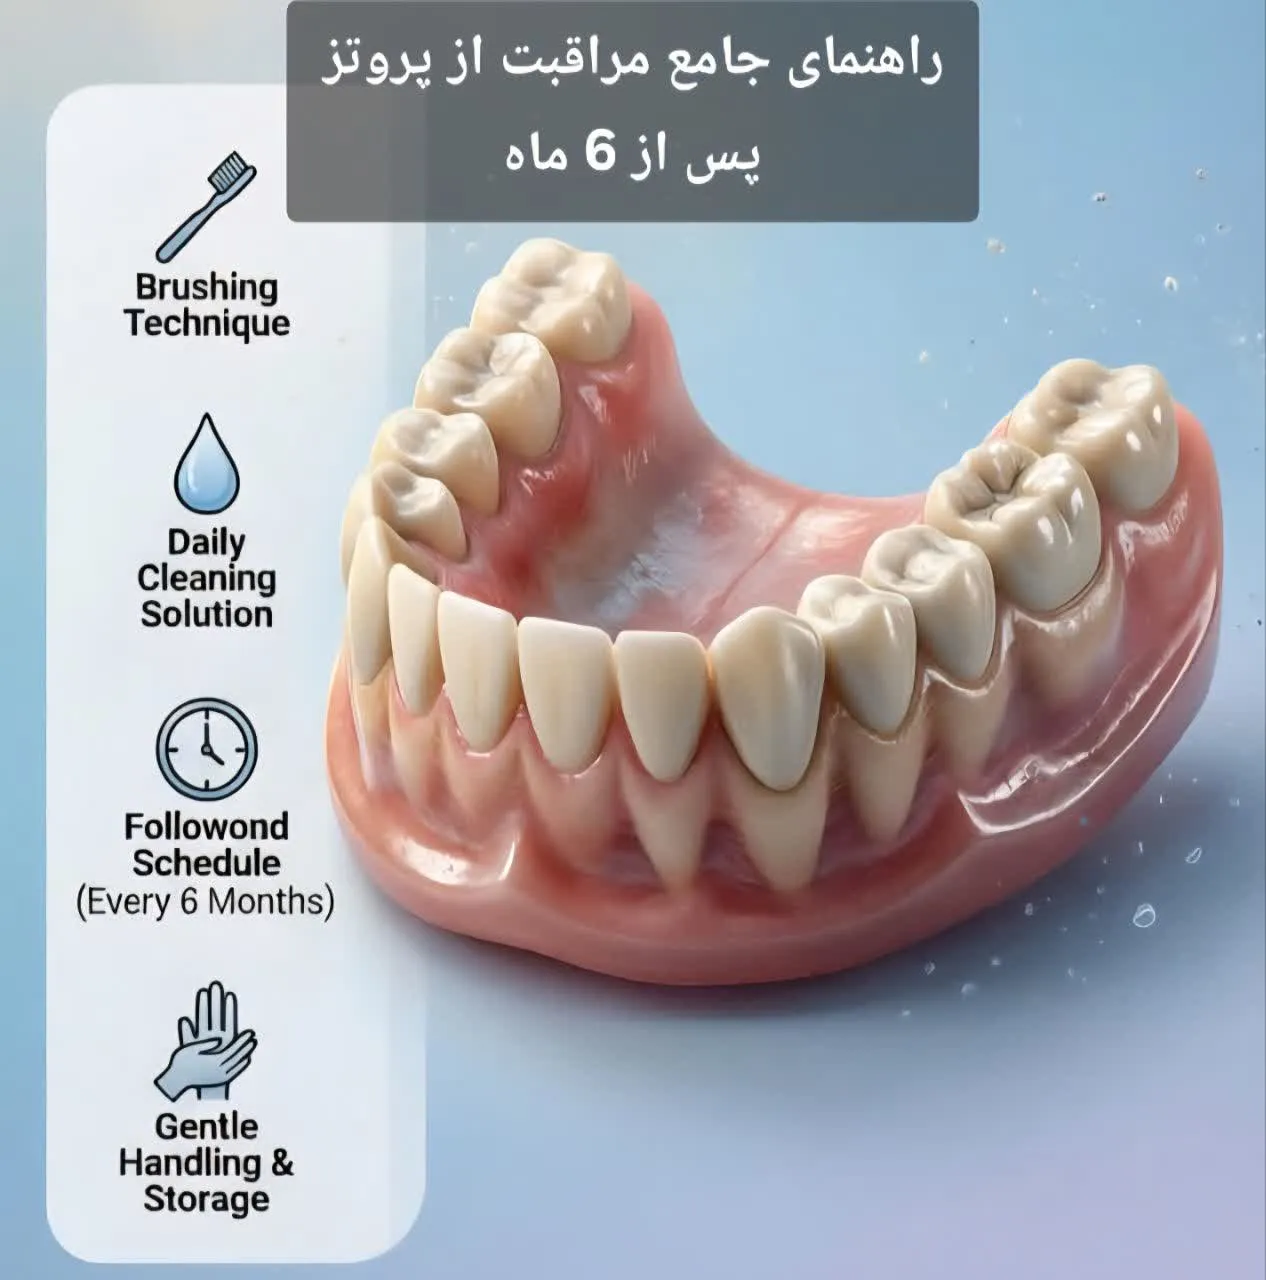

پروتزهای دندانی، چه ثابت و چه متحرک، نقش بسیار مهمی در بازگرداندن عملکرد طبیعی دهان، زیبایی لبخند و اعتمادبهنفس بیماران دارند. با این حال، بسیاری از بیماران تصور میکنند پس از گذشت چند ماه از نصب پروتز، دیگر نیازی به مراقبتهای ویژه نیست؛ در حالی که مراقبت از پروتز پس از ۶ ماه یکی از حساسترین و مهمترین مراحل در حفظ سلامت دهان و افزایش طول عمر پروتز به شمار میرود. در این بازه زمانی، پروتز با محیط دهان سازگار شده، اما همزمان ممکن است تغییرات ظریفی در لثه، استخوان فک یا حتی ساختار خود پروتز ایجاد شود که بدون مراقبت صحیح، به مشکلات جدیتری منجر خواهد شد.

هدف این مقاله ارائه یک راهنمای جامع و تخصصی برای مراقبت از پروتز پس از گذشت شش ماه است تا بیماران بتوانند با رعایت اصول علمی و توصیههای دندانپزشکی، از بروز عفونت، لق شدن پروتز، تحلیل لثه و هزینههای درمانی اضافی جلوگیری کنند.

مراقبت روزانه از پروتز پس از شش ماه

مراقبت از پروتز باید بهصورت روزانه و منظم انجام شود و محدود به چند هفته اول پس از نصب نیست. در این مرحله، رعایت بهداشت دهان و پروتز اهمیت دوچندان دارد، زیرا پلاکهای میکروبی بهراحتی میتوانند در اطراف پروتز تجمع پیدا کنند.

تمیز کردن پروتز باید حداقل دو بار در روز انجام شود. برای پروتزهای متحرک، خارج کردن آنها از دهان و شستوشوی کامل با آب ولرم و شویندههای مخصوص پروتز توصیه میشود. استفاده از خمیردندانهای معمولی به دلیل خاصیت سایندگی بالا میتواند به سطح پروتز آسیب بزند و باعث ایجاد خراشهای میکروسکوپی شود که محل تجمع باکتریها خواهد بود.

در پروتزهای ثابت، استفاده از نخ دندان مخصوص (Super Floss)، برسهای بیندندانی و واترجتها نقش مهمی در تمیز کردن نواحی غیرقابل دسترس دارد. این ابزارها به حذف ذرات غذایی و پلاک از زیر روکشها و اطراف لثه کمک میکنند و از التهاب لثه جلوگیری مینمایند. رعایت این اصول ساده اما حیاتی، پایه اصلی مراقبت از پروتز در بلندمدت است.

مراجعات دورهای؛ بخش جدانشدنی مراقبت از پروتز

حتی اگر هیچگونه درد یا ناراحتی احساس نمیکنید، مراجعه منظم به دندانپزشک هر شش ماه یکبار بخش ضروری مراقبت از پروتز است. در این جلسات، وضعیت پروتز، سلامت لثه، میزان تطابق آن با فک و وجود هرگونه نشانه پنهان عفونت یا تحلیل بررسی میشود.

مراقبت از پروتز پس از ۶ ماه نهتنها به حفظ ظاهر و عملکرد آن کمک میکند، بلکه نقش مستقیمی در سلامت لثهها، استخوان فک و کیفیت زندگی بیمار دارد. رعایت بهداشت روزانه، تغذیه مناسب، توجه به علائم هشداردهنده و مراجعه منظم به دندانپزشک، چهار ستون اصلی مراقبت صحیح از پروتز هستند. با رعایت این اصول، میتوانید سالها بدون دردسر از پروتز خود استفاده کنید و از لبخندی سالم و مطمئن لذت ببرید.